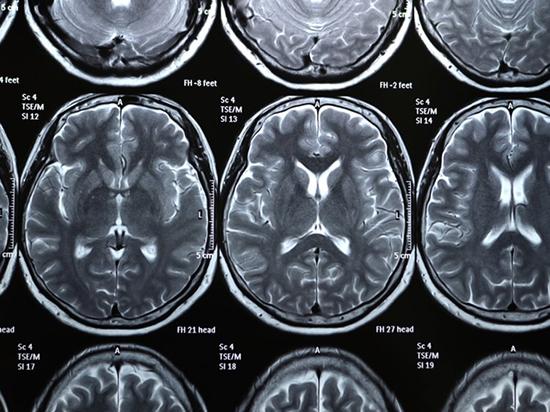

با عجایب شگفتانگیز مغز آشنا شوید

شما هر روز و هر شب از مغز خود استفاده میکنید، اما تا چه اندازه در مورد سیستم مغز و نحوه عملکرد آن آگاهی دارید؟ قرنهاست که دانشمندان بدنبال بررسی و انجام آزمایشات گوناگون روی مغز انسان هستند تا بتوانند رازهایی زیادی در مورد آن را کشف کنند. تا به امروز نیز مسایل جذاب و شگفتیهای زیادی در مورد یکی از اصلیترین اعضای بدن انسان را کشف شده است. برای آشنا شدن با واقعیتهای عجیب و جالب در مورد سلولهای خاکستری مغز در ادامه با ما همراه باشید.